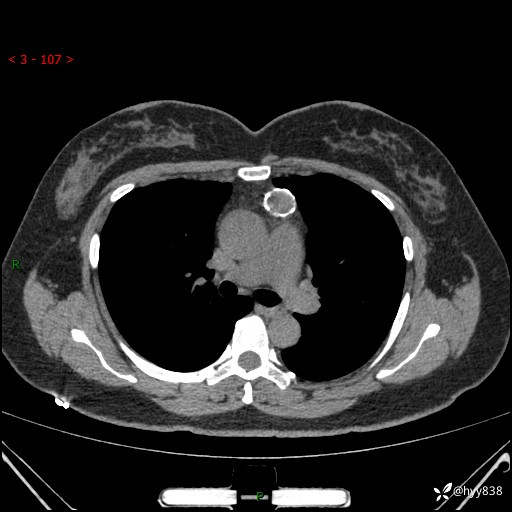

中年女性,检查发现纵隔占位3月余。圆圆的肿物,周围环绕一圈钙化---结果公布~

主诉:检查发现纵隔占位3月余。

现病史:患者于3月前体检行胸部CT检查发现纵隔占位,患者平素无明显咳嗽咳痰,无心慌、胸闷、胸痛、呼吸困难、低热、盗汗,无头痛、头晕,无腹痛、腹胀等不适。现患者欲求进一步治疗,遂来我院就诊,以“纵隔占位”收入我科。 患者自起病以来,精神可,睡眠可,饮食可,大小便正常,体重无明显改变。

胸部CT平扫+增强